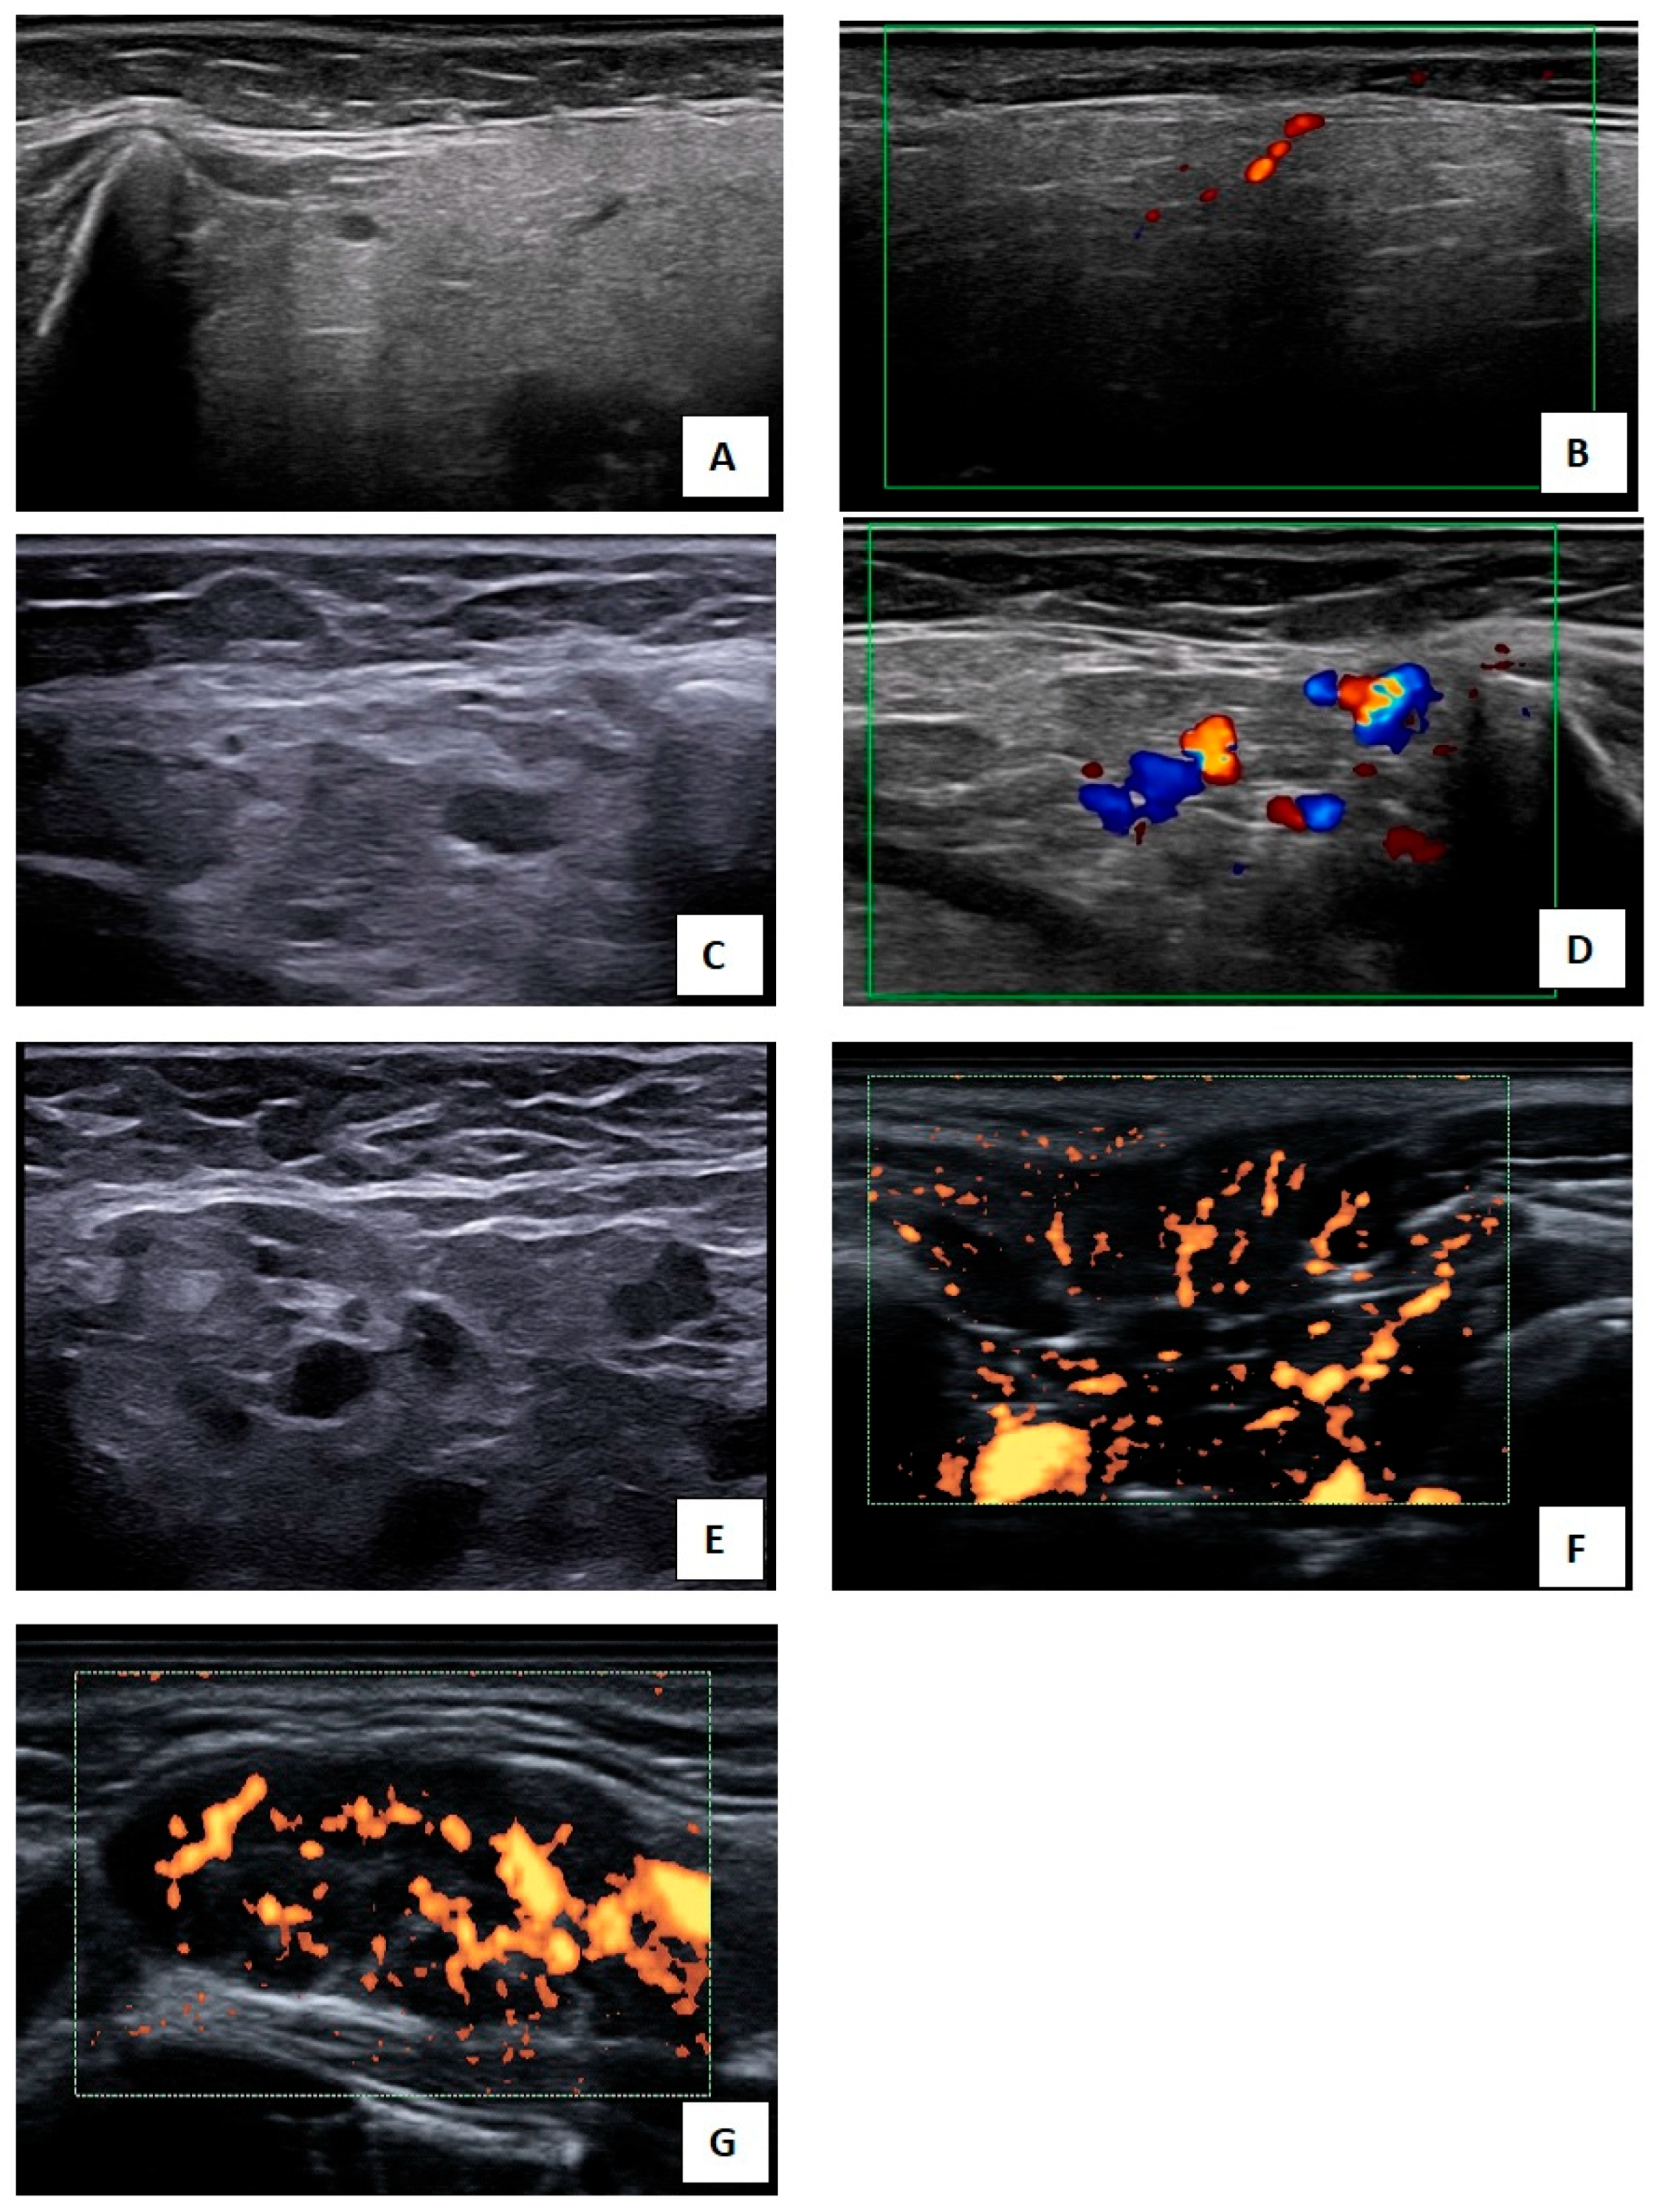

2.2.3. US Examination

2.2.4. Salivary Gland Ultrasound (SGUS)